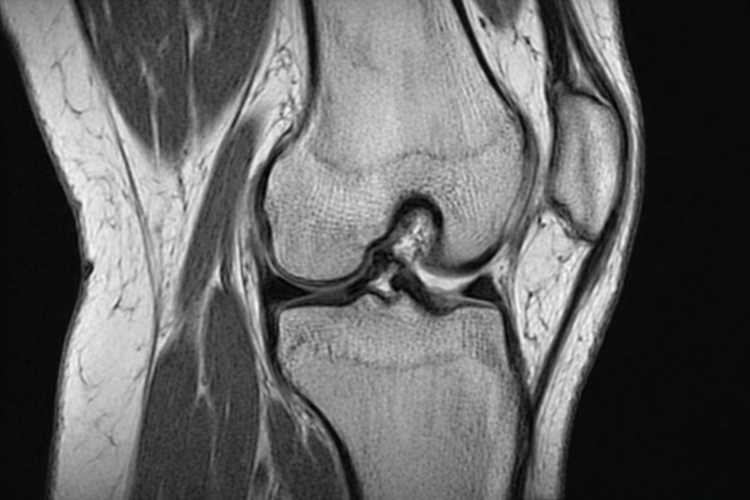

Coronal MRI scan of knee showing joint structures for injury assessment.

Imaging is often used alongside the physical examination to confirm the diagnosis and assess the extent of injury:

• X-rays assess bone alignment and help rule out fractures but do not show soft tissue injuries such as ligament or meniscus tears.

• MRI (magnetic resonance imaging) provides detailed images of ligaments, menisci, cartilage, and tendons, and is commonly used for knee sports injuries.

• Ultrasound is used to assess tendons and superficial structures and may be useful for conditions such as patellar tendinopathy.

In some cases, diagnosis may be confirmed during knee arthroscopy, a minimally invasive surgical procedure in which a small camera is inserted into the joint. This allows direct visualisation of internal structures and, where appropriate, treatment during the same procedure.